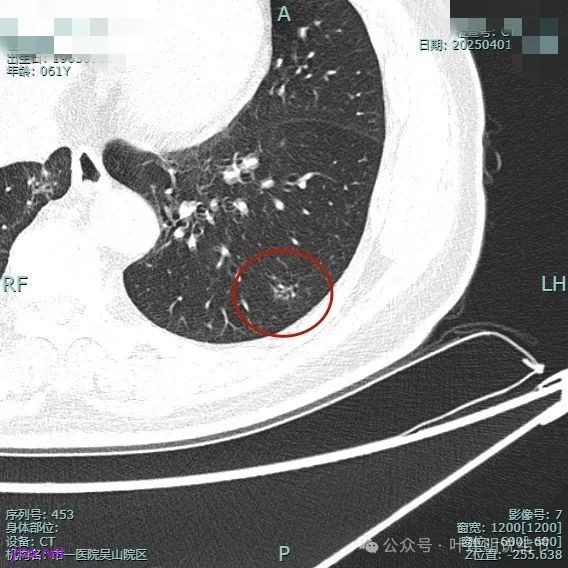

病灶毛刺空泡(或细支气管扩张)都有,表面不平,灶内杂乱。

但纵向看是偏条状些的,密度较高,边上有少许磨玻璃成分,磨玻璃部分略显模糊。

中间实性部分密度过高,边上的的毛刺显得过长,且不太锐利。

实性成分密度较高,边上有淡磨玻璃成分,毛刺明显。

密度高,边上磨玻璃成分淡,表面不平,毛刺不太锐利,整体感觉缺乏收缩力。

相应支气管有扩张,边上的磨玻璃成分偏糊,界限欠清。

进入的血管没有异常增粗,棘突不太锐利,磨玻璃成分偏糊。

上图倒是血管显得有点异常增粗的,总体膨胀性不强,收缩力不够。

我的意见是纵向看线状,考虑慢性炎伴纤维增生可能性大些,建议4-6个月复查。